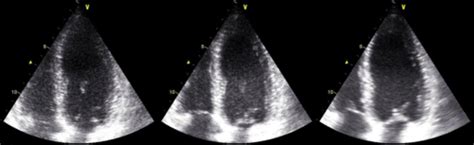

Alright, let’s get down to brass tacks: what exactly is diagnostic imaging ? In its simplest form, it’s the non-invasive process of creating visual representations of the interior of a body for clinical analysis and medical intervention. These images help doctors visualize internal structures, diagnose diseases, monitor existing conditions, and even guide medical procedures. Imagine you have a mysterious pain, and your doctor needs to see if it’s a muscle strain, a bone fracture, or something else entirely. That’s where diagnostic imaging comes in handy! It provides crucial visual evidence that simply cannot be gathered through a physical examination alone. We’re talking about technologies like X-rays, CT scans, MRIs, and ultrasounds – each offering a unique window into different aspects of your internal health. The importance of diagnostic imaging for your health cannot be overstated. It’s often the first critical step in figuring out what’s going on when you’re not feeling your best, or even when you’re just trying to get a baseline for your overall wellness. Early and accurate diagnosis is often the key to effective treatment and better outcomes, and that’s precisely what diagnostic imaging facilitates. Think about it: if you can spot a problem like a tumor or an internal injury early, the chances of successful treatment skyrocket. It’s also instrumental in preventing unnecessary invasive procedures by providing clear, detailed images that guide medical decisions. So, for anyone wondering about their health or facing a medical mystery, understanding the power of diagnostic imaging is super important. It’s not just about finding what’s wrong; it’s about empowering you and your healthcare team with the information needed to maintain your health, manage chronic conditions, and ultimately, live a longer, healthier life. Trust me, guys, these technologies are far from just a doctor’s tool; they are a fundamental pillar of modern healthcare, making sure we get the best possible insights into our physical well-being. It’s a huge part of proactive health management and ensures that your medical journey is as informed and effective as possible, from initial symptoms to recovery.

Let’s really zoom in on why diagnostic imaging is so utterly crucial in modern healthcare. It’s not just a fancy add-on; it’s the very bedrock for informed medical decision-making across almost every specialty. From emergency rooms to routine check-ups, diagnostic imaging provides indispensable insights that shape treatment plans, monitor disease progression, and even guide complex surgeries. Think about someone who comes into the ER after an accident. Doctors immediately need to know if there’s internal bleeding, organ damage, or broken bones. A quick CT scan or X-ray, both forms of diagnostic imaging , can provide those answers in minutes, potentially saving a life. Beyond emergencies, consider the chronic conditions that so many people manage, like heart disease or cancer. Regular diagnostic imaging allows doctors to monitor the size of a tumor, check the effectiveness of chemotherapy, or assess the health of a patient’s heart over time. This continuous feedback loop is absolutely essential for adjusting treatments and ensuring patients are getting the best possible care. It also plays a monumental role in preventative care . For instance, mammograms (a type of X-ray) are a key diagnostic imaging tool for early detection of breast cancer, often finding abnormalities years before they can be felt. This early detection drastically improves survival rates. Furthermore, diagnostic imaging assists in interventional procedures, like biopsies, by giving surgeons and specialists a real-time visual guide. This precision minimizes invasiveness and improves patient outcomes. The ability to